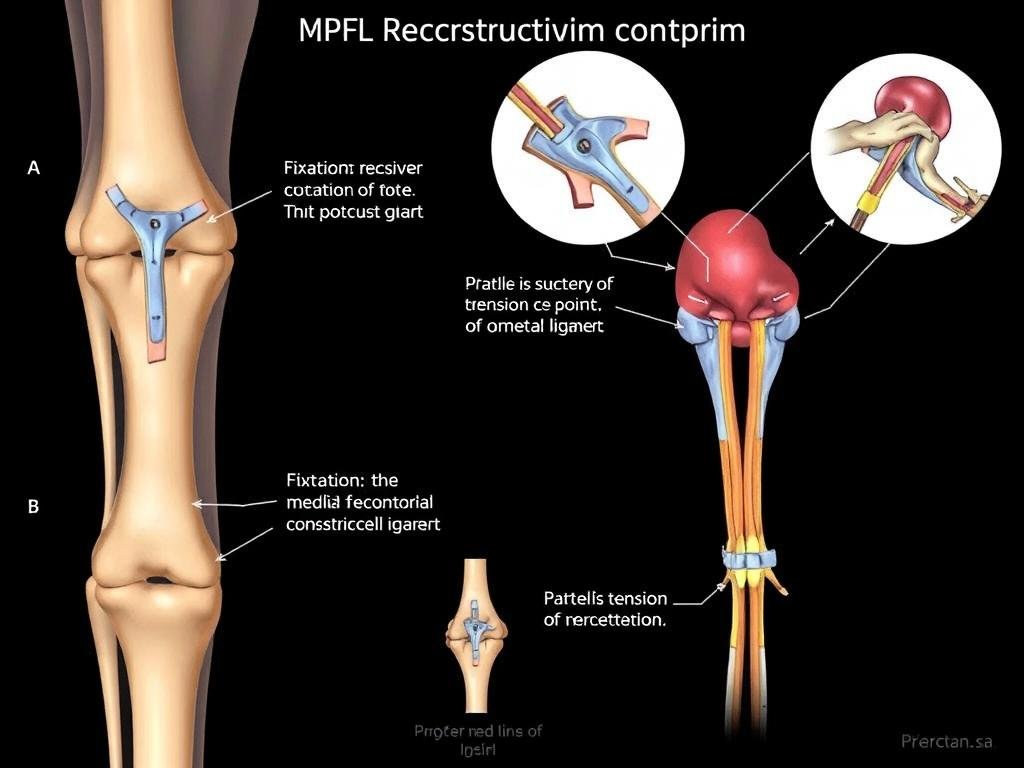

Operative Rekonstruktion des medialen patellofemoralen Ligaments (MPFL) zur Stabilisierung der Kniescheibe

MPFL-Rekonstruktion

Die Rekonstruktion des medialen patellofemoralen Ligaments (MPFL) ist heute das Standardverfahren bei wiederkehrenden Patellaluxationen:

- Prinzip: Das gerissene innenseitige Halteband der Kniescheibe wird durch eine Sehne (meist aus dem eigenen Körper) ersetzt

- Vorteil: Hohe Erfolgsrate mit über 80% Beschwerdefreiheit bei rechtzeitiger Durchführung

- Durchführung: Minimalinvasiv mit kleinen Schnitten und arthroskopischer Kontrolle

- Nachbehandlung: Schrittweise Belastungssteigerung über 6-12 Wochen

Schematische Darstellung der MPFL-Rekonstruktion: Ersatz des gerissenen Bandes durch eine Sehne